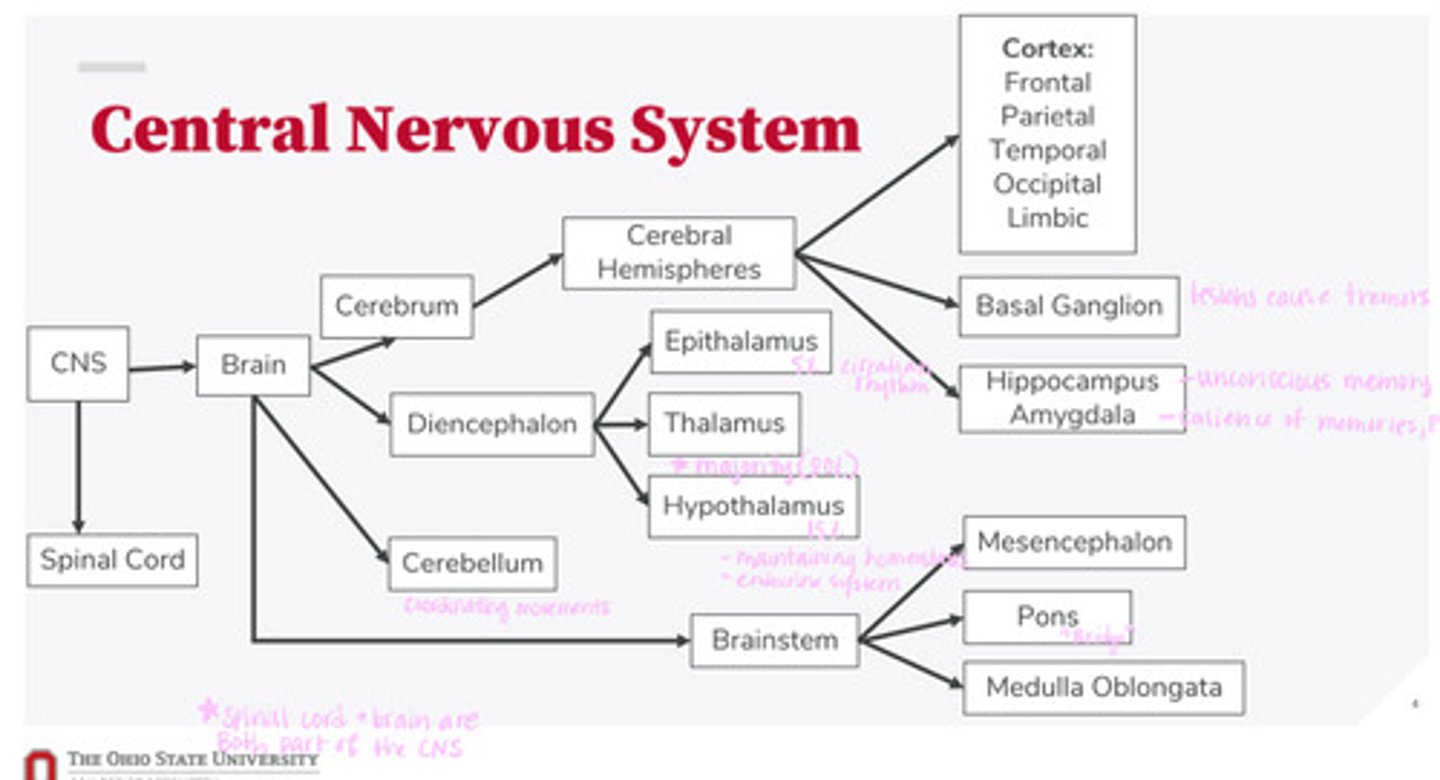

-brain

-spinal cord

What are the 2 divisions of the CNS?

-cerebrum

-diencephalon

-cerebellum

-brainstem

What are the 4 divisions of the brain?

-epithalamus

-thalamus

-hypothalamus

What are the 3 divisions of the diencephalon?

-mesencephalon

-pons

-medulla oblongata

What are the 3 divisions of the brainstem?

-cortex

-basal ganglion

-hippocampus

-amygdala

What are the divisions of the cerebral hemispheres?

-frontal lobe

-parietal lobe

-temporal lobe

-occipital lobe

-limbic system

What are the divisions of the cortex?

coordinating movements

What is the function of the cerebellum?

thalamus

A majority of signals from the diencephalon flow into where?

circadian rhythm

What is the function of the epithalamus?

-maintaining homeostasis

-endocrine system function

What is the function of the hypothalamus?

tremors

Lesions on the basal ganglion cause what?

hippocampus

What part of the brain is in control of unconscious memory?

amygdala

What part of the brain is in control of the salience of memories (PTSD)?

The bridge between the mesencephalon and the medulla oblongata

What is the function of the pons?